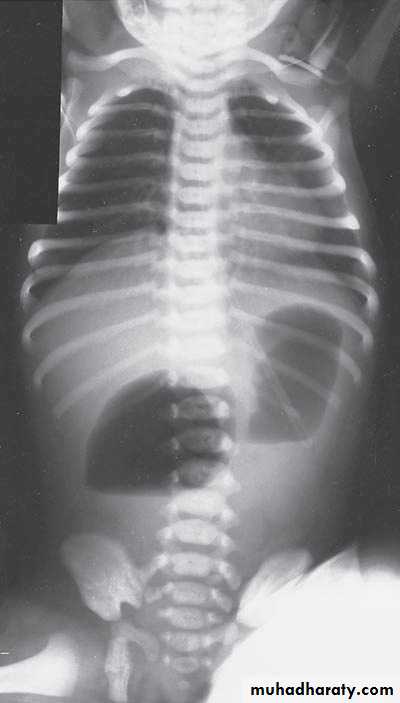

Scaphoid abdomen

Diaphragmatic eventration